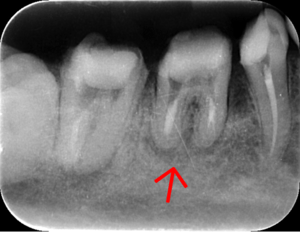

レントゲン写真

- 透過像

| 治療方針 | 右下の当該歯は歯根破折により保存不可能と診断しました。歯周疾患も伴っていたため抜歯後に骨吸収※1が大きく起こることが予測できました。チタンメッシュ併用骨再生誘導法(GBR※2)を選択しインプラント埋入と同時に行い自然な歯槽骨のラインを再現しました。またGBRを行う際にインプラント辺縁の付着歯肉の減少が起こる為、遊離歯肉移植術(FGG※3)を行い清掃性を考慮した形態に仕上げました。 ■治療方針の解説 治療した右下の歯をレントゲンで撮影したところ根本の部分に黒く写る箇所があり「根尖性慢性周囲炎※1」と診断。また歯周病も進行していました。 ※1 骨吸収・・・歯槽骨という歯を支える骨がなくなっていくこと |